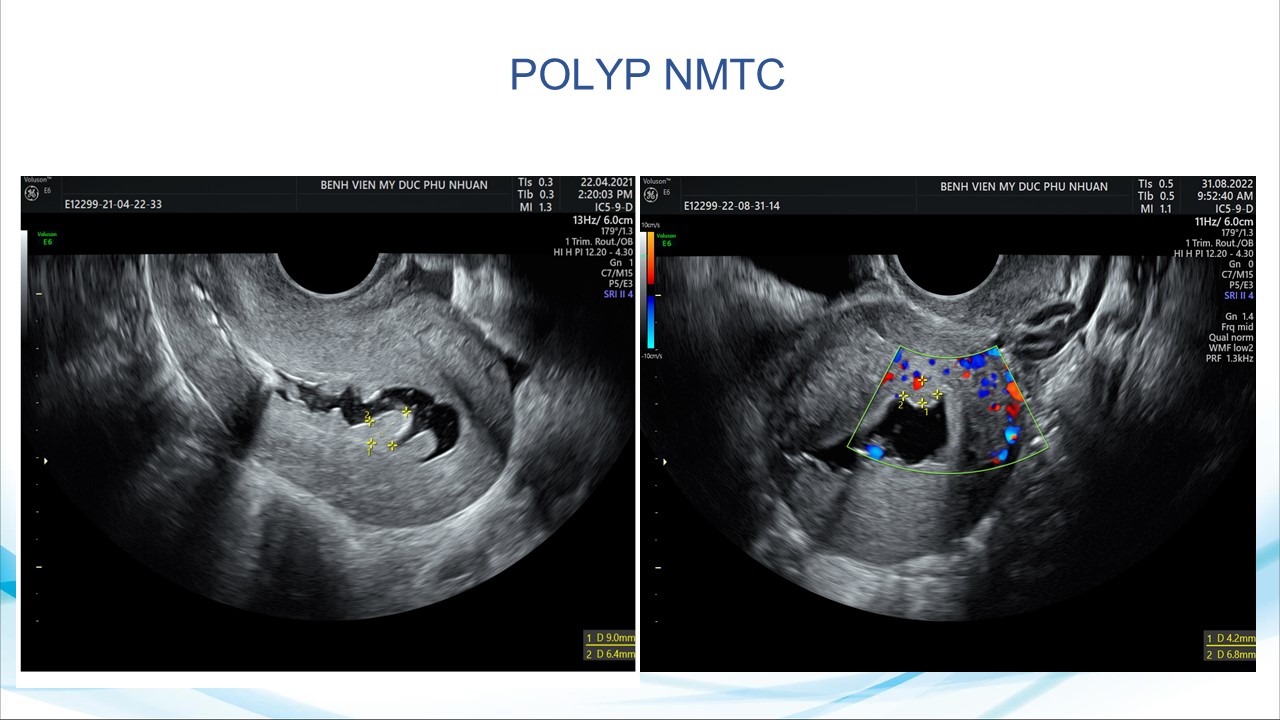

Siêu âm sử dụng chật tương phản trong phụ khoa